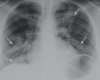

Q

A

Consolidación alveolar

How well did you know this?